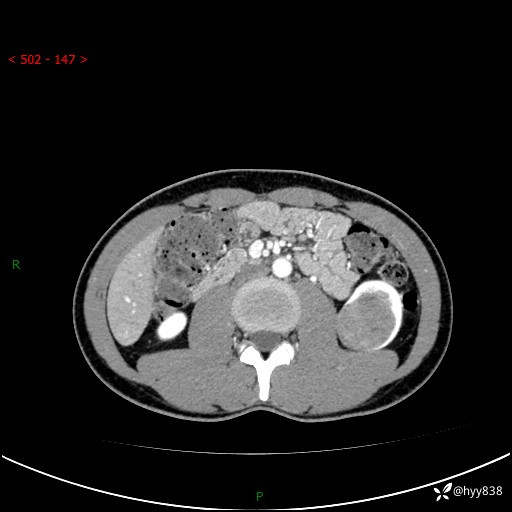

年轻男性,发现左肾占位1天。“非好病例”我不发,误诊率高---(有结果)

现病史:患者昨日中午进食后出现明显腹痛,腹泻,在我院急诊科行补液及对症治疗,双肾输尿管彩超提示左肾占位(5.2*4.3cm),平素无明显腰痛,无再发肉眼血尿等情况,现为求处理左肾占位,遂来我院,门诊以左肾占位收治入院。 患者起病以来,精神、食欲、睡眠尚可,大便可,小便如上,体力体重无明显下降。

双肾CT平扫+增强(三期)